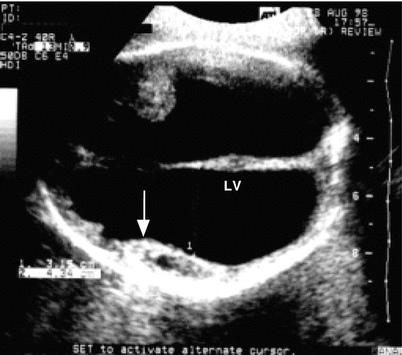

Fig. 15.4

Cross-section of the cephalic pole showing dilatation of the lateral ventricles (LV) and residual brain parenchyma (arrow) in a fetus with toxoplasmosis